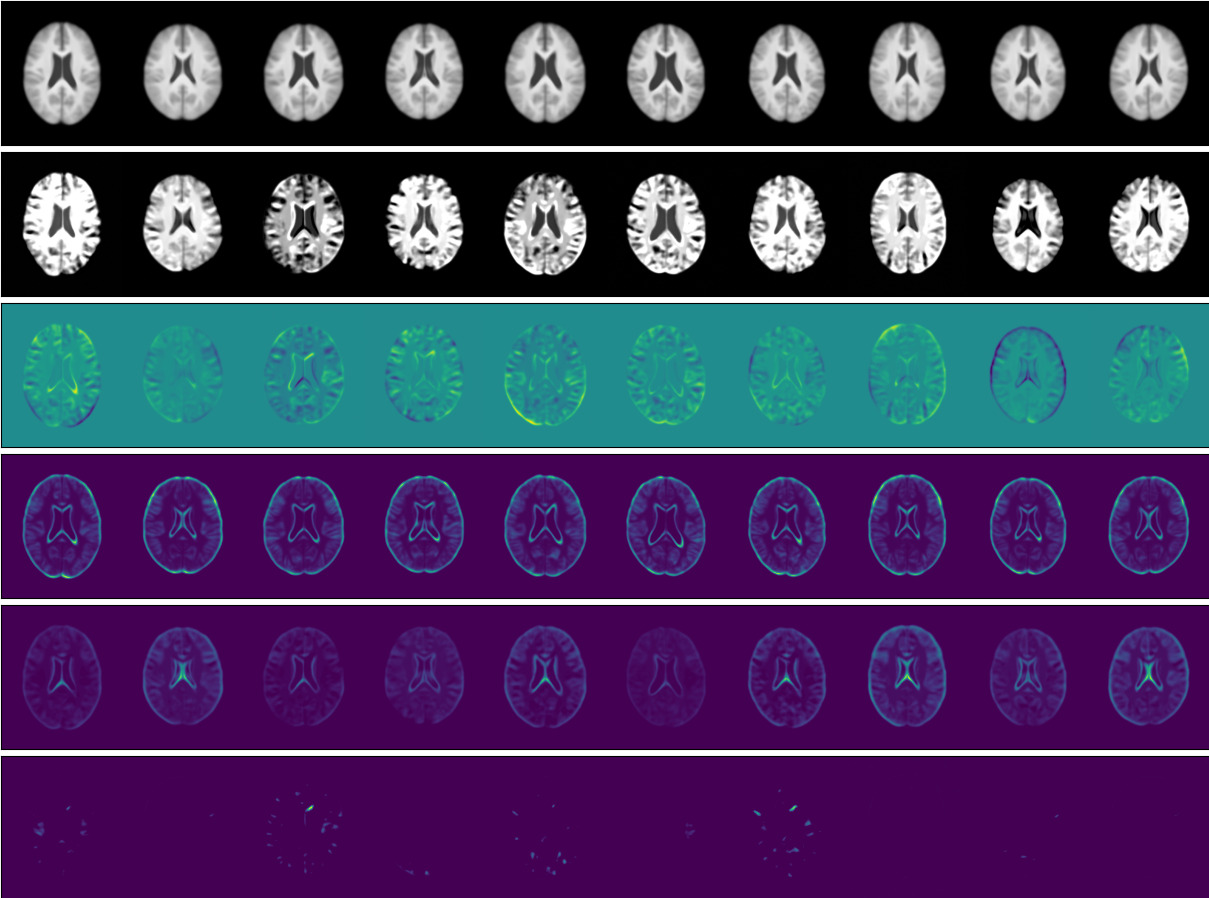

We start by comparing a -VAE, with a pixel-wise independent normal observational distribution, to the proposed SOS-VAE method, with a low-rank multivariate normal observational distribution. We choose a -VAE (Higgins et al., 2017) baseline rather than a standard VAE so that it can be trained using the same Lagrangian method with being a Lagrangian multiplier. This allows for fairer testing since the comparison is between models that differ only by our contributions. This is the only modification to the baseline over a standard VAE. We perform the comparison in two datasets: the CELEBA dataset (Liu et al., 2015) and the UK Biobank (UKBB) Brain Imaging dataset (Miller et al., 2016). For all models, we use a latent space of dimension 128. For the low-rank model, we use a rank of 25. For the CELEBA dataset we use a target KL loss , , of 45 for both models and for our model. For the UKBB dataset we use a target KL loss, , of 15 for both models and for our model. Figures 2(a) & 2(b) and 2(c) & 2(d) show the qualitative results for the comparison.

In Figures 2(a) and 2(c), we see that the samples of the -VAE exhibit uncorrelated pixel noise around the mean, resulting from the pixel-wise independent joint observational distribution. In contrast, in Figures 2(b) and 2(d), we see that the samples produced by our SOS-VAE contain semantically-meaningful variations around the mean and are spatially coherent, as illustrated in the difference (row 3) between the mean (row 1) and the sample (row 2). Looking at the variance of the two methods (row 4), we see a significant difference in the regions where each model is uncertain, highlighting the difference in behaviour between the two predicted distributions. The predicted covariance (rows 5 and 6) for the low-rank model contains a structure that pertains to the image content. These figure rows represent positive and negative covariance to the central pixel indicating global covariance can is modelled. This structure results in spatially coherent samples as opposed to the noisy samples of the -VAE, which are a consequence of the diagonal covariance. Interestingly, we observe more variation in the means of the -VAE, suggesting that as more variation can be modelled in the observation space, less needs to be modelled in the latent space.